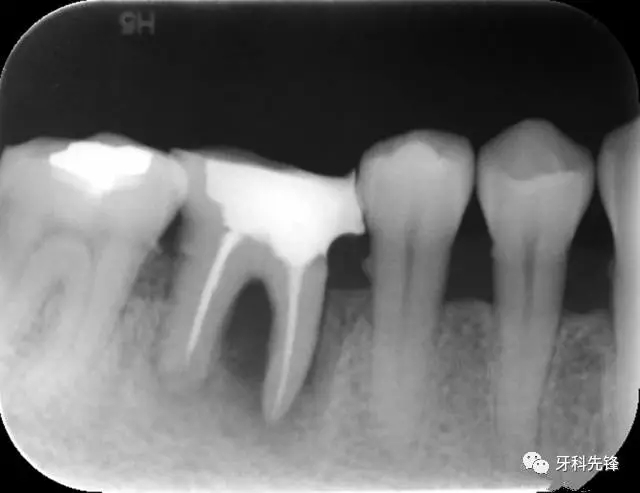

圖8治療術(shù)后X光片

640.webp (10).jpg

640.webp (11).jpg

640.webp (12).jpg